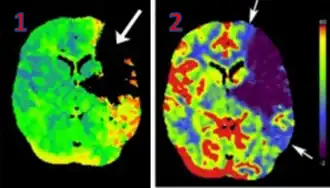

CT Perfusion plays an important role in the assessment of Acute Ischemic Stroke. It is used to create maps of blood flow, blood volume, and mean transit time to assess the tissue and to differentiate between the core and penumbra in stroke.[3]